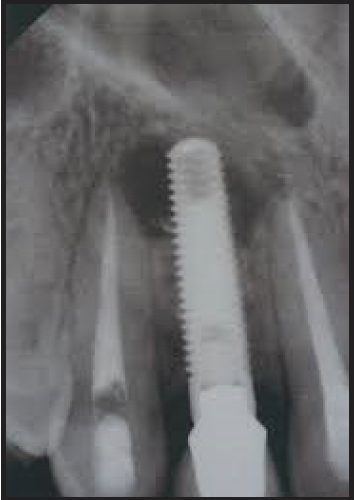

Periapical Radiographic Images

The purpose of the intraoral periapical examination is to obtain a view of the entire tooth and its surrounding structures, as in Figure 1. Two exposure techniques may be employed for periapical radiography: the paralleling technique and the bisecting angle technique. The paralleling technique is the preferred method. This technique provides less image distortion and reduces excess radiation to the patient. The paralleling technique should always be attempted before other techniques. The bisecting technique can be employed for patients unable to accommodate the positioning of the paralleling technique. Candidates may include those with low palatal vaults and children. Disadvantages to the bisecting technique include image distortion and excess radiation due to increased angulations involving the eye and thyroid glands. Regardless of the technique, however, the rules of radiography referred to earlier must be followed.

Figure 1 - Periapical Image

Figure 1